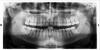

pipek Опубликовано 22 февраля, 2013 Поделиться Опубликовано 22 февраля, 2013 Всем добрый день!На днях удалили 18 зуб. (очень болел, и по причине 8-ки не стал разбираться и удалил - оказалось кариес проел дырку со стороны кармана).Хирург при удалении сказал, что между 17 и 18 был очень большой карман и разъелась костная ткань и рекомендовал удаление 17 ого.Я удивился (жалко как-то здоровый зуб) и пошел к другому врачу. Тот посмотрев - сказал надо в нем лечить кариес - 15 000 р. Пошел к еще одному - тот сказал лечить карман, отказавшись даже смотреть снимки..Я запутался ) Сколько врачей - столько и мнений.На данный момент между 16 и 17 образуется карман, где уже застревает пища. Подвижность зуба - не ощущаю. Вопрос, вечный: что делать ? PS Все твердят, что зубы нужны когда парами идут, то есть 8-ку вырвал - убирай и его пару. Это так ? Ссылка на комментарий

IvanK Опубликовано 22 февраля, 2013 Поделиться Опубликовано 22 февраля, 2013 в Вашем случае я бы советовал подождать недельку - пусть заживет лунка 18, далее сходить к терапевту на консультацию по поводу возможности лечения 17.28 нужно удалять (функционального толка в нем нет, а проблем доставить может..) .По поводу нижней правой 8-ки - нужно смотреть в полости рта+ консультация пародонтолога Ссылка на комментарий